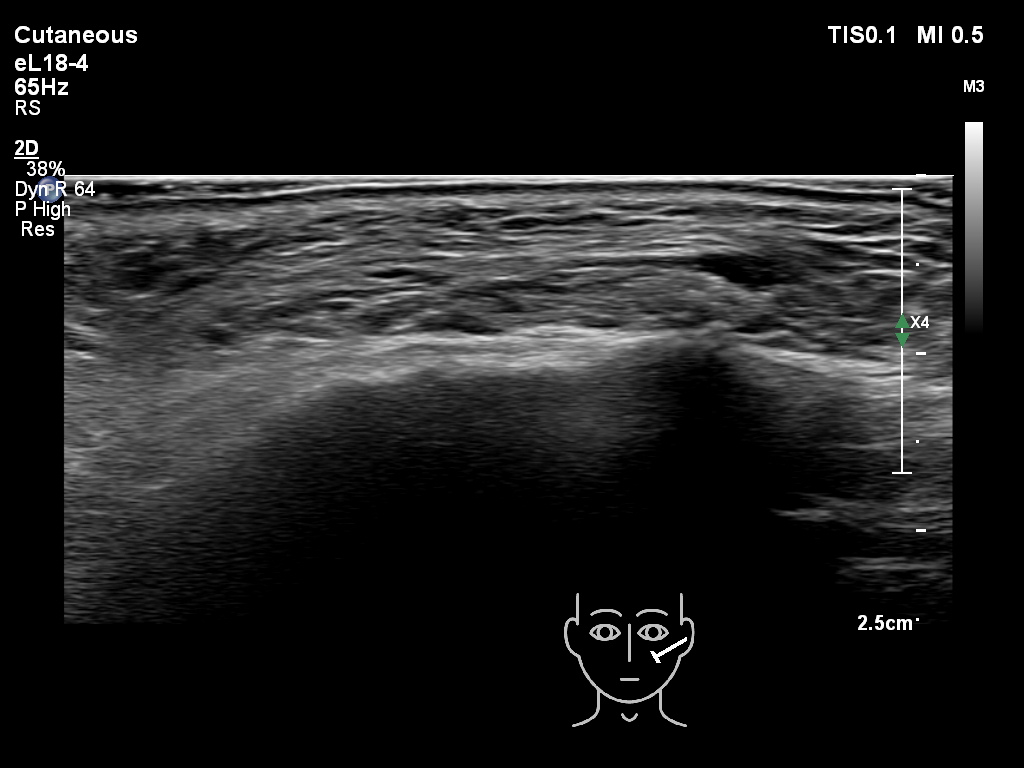

Fillers

Draw in the image on the right where the fillers are located. To check if your answer is correct, please click on the secondary image.